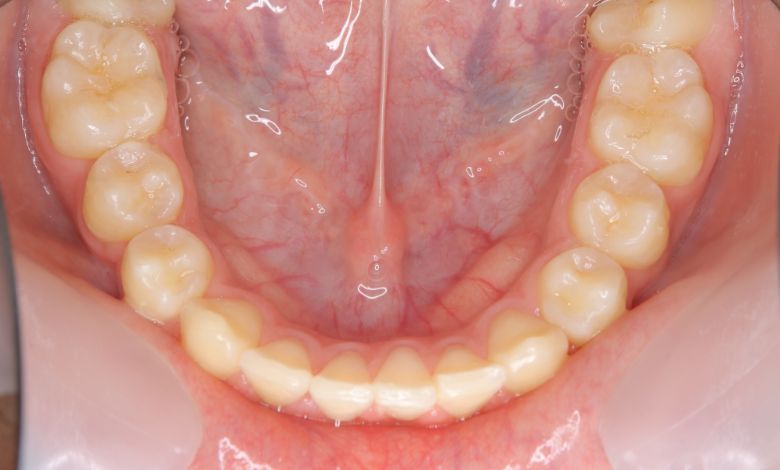

叢生が解消され、歯列全体にわたり滑らかで調和のとれた配列が得られています

術前に認められた前歯3本の強い重なりは完全に解消され、スムーズな歯列が形成されました。

精密検査の結果、抜歯を行わずに歯列弓を拡大する治療方針を選択。歯が正しい位置に並ぶスペースを

確保したことで、歯列は自然なU字型に整い、叢生が解消されました。見た目の改善だけでなく、

咀嚼機能の向上や清掃性の改善といった機能面での効果も期待できます。

歯列弓の側方拡大により適切なスペースが確保され、歯が綺麗に並んでいます